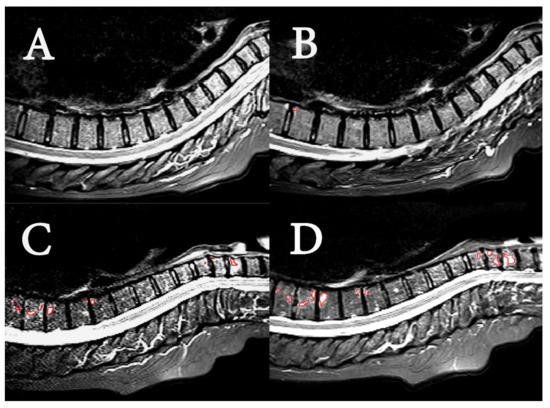

- Radiological evaluation

- Image pre-processing and textural feature extraction

- Textural features